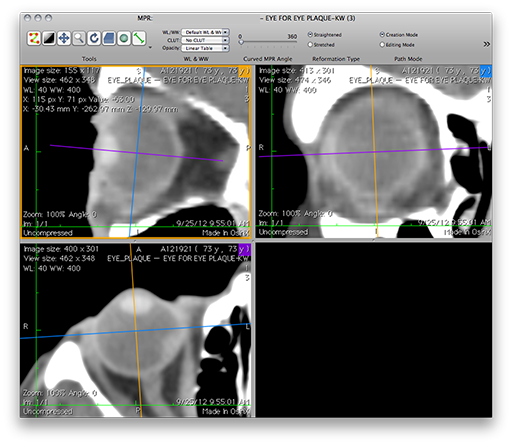

Multiplanar reconstruction using OsiriX

The recommended method of preparing CT and MR images for Plaque Simulator is to use the OsiriX application to create up to 5 multiplanar reconstructions from an axial 3D series of DICOM compatible image files. The spacing between slices should be as small as possible (3 mm maximum) without losing soft tissue image quality. Try to avoid using high speed protocols that result in grainy images of the soft tissues of the eye.

Follow this link to the OsiriX Tutorial.

OsiriXOrthogonalPlanes.png